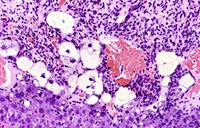

This hemangiosarcoma is poorly demarcated from surrounding parenchyma and consists of dilated blood-filled spaces and sheets of proliferating endothelial cells.